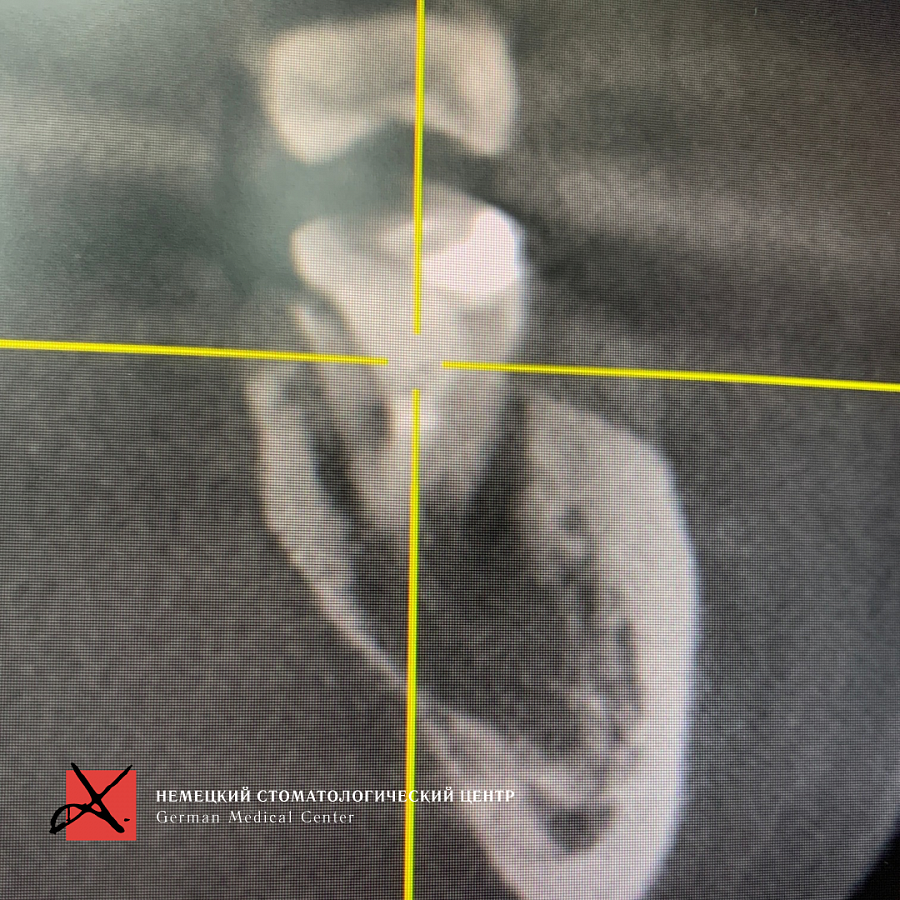

На рентгеновском снимке видим разрежение костной ткани, обширный воспалительный процесс, который находится в контакте с нижним челюстным каналом. В канале проходит нерв, вена и артерия.Этапы лечения

Принято решение удалить зуб и провести щадящий кюретаж с целью не повредить нижний челюстной нерв, т.к. это может привести к онемению губы и подбородка.